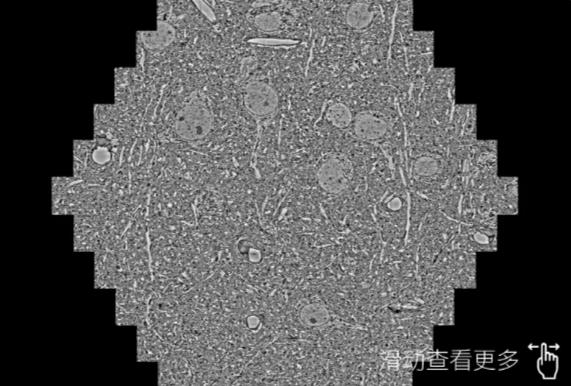

鼠脑切片。左图使用南昌蔡司南昌扫描电镜MultiSEM706对165μmx143pm面积区域成像,耗时仅需1.5秒。右图为鼠脑切片中30μm区域放大效果。样品由芝加哥大学B.Kasthuri提供。

使用蔡司高速南昌扫描电镜MultiSEM对1mm²人脑皮层组织进行高分辨成像,并对其中的各种细胞结构进行三维重构分析。左图展示了2x3mm²组织平面中锥体神经元的三维重构效果。右图显示了局部体积神经元三维重构。图像由哈佛大学chtman实验室提供,渲染图由D. Berger 制作。